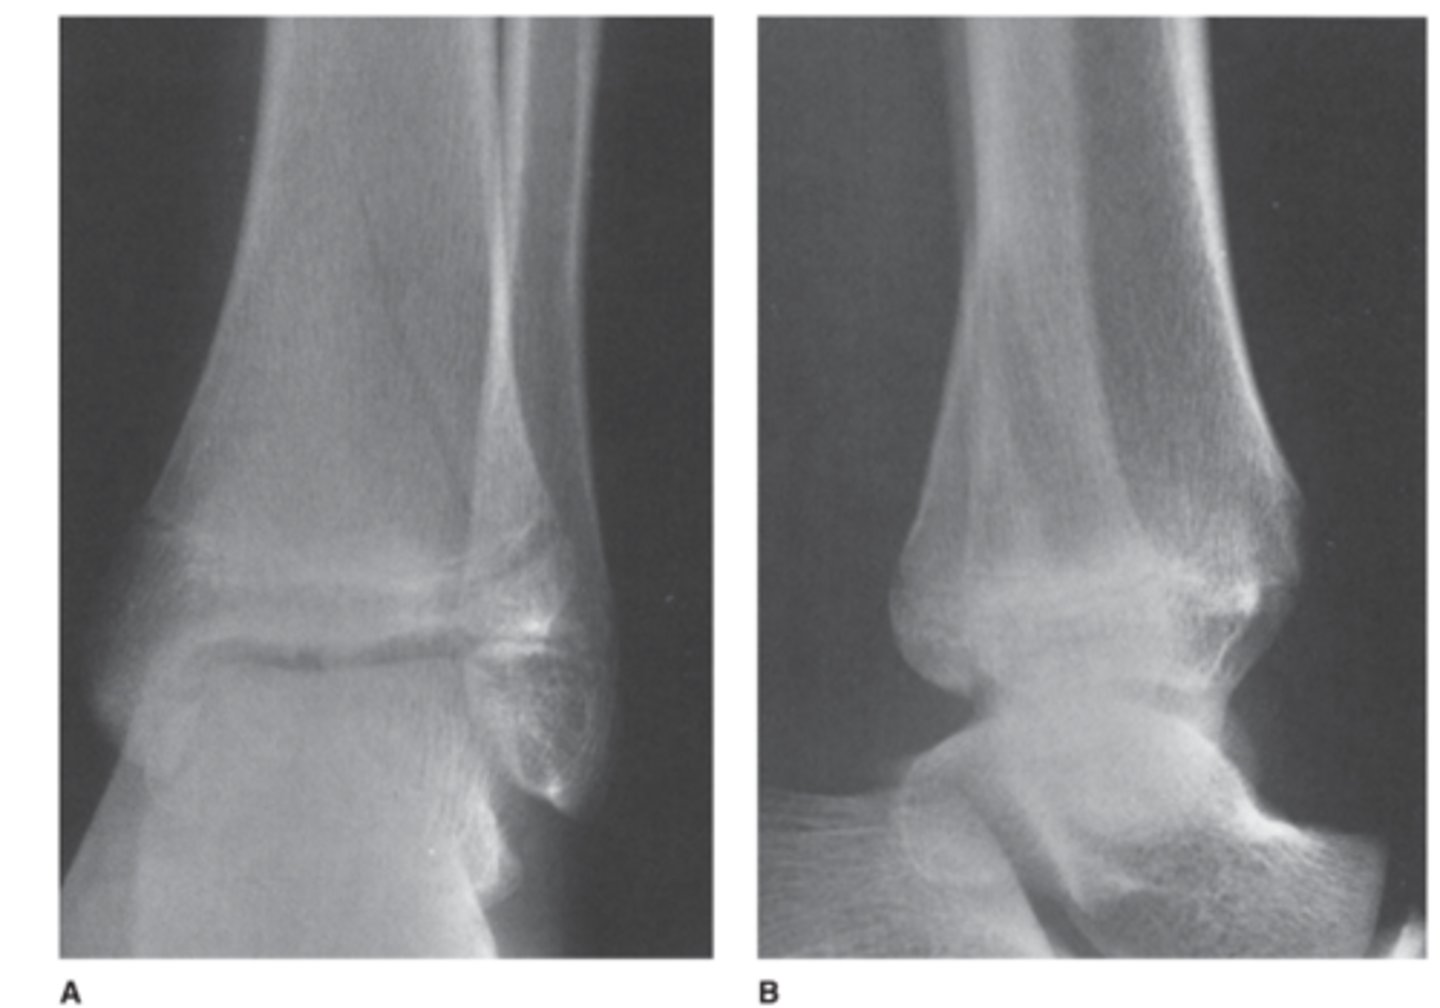

A 15-year-old boy complains of ankle pain after a fall (AP and lateral views of the ankle).

What is the abnormality in Case 6-5 (Figure 6-12)?

A. Sprain of the lateral ligaments

B. Fracture of the distal fibula

C. Stress fracture of the talus

D. Triplane fracture of the distal tibia

Answer

D.

Note how the lucencies rule vertically through the epiphysis and obliquely through the metaphysis. This is also called a Salter Harris IV fracture

Salter Harris IV fracture

-Triplane fracture

-Goes through all three the epiphyses, physes, and metaphyses